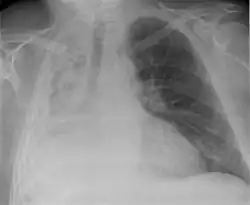

Atelectasis

Atelectasis is the partial collapse of a lung that is reversible. There are numerous etiologies, including post-operative atelectasis, surfactant deficiency, mucus plugging, and foreign body aspiration. Notably, post-operative atelectasis is thought to be caused by general anesthesia administration. Collapse of the affected lung shifts mediastinal structure towards the same side and can be observed on chest x-ray or CT. Radiographic features include increased opacification of collapsed lung and/or tracheal shift.[14]